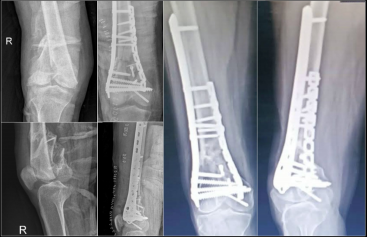

2.雙鋼板固定

目前,雙鋼板固定或釘板聯合固定形式已成為大多數老年股骨遠端骨折的首選治療方法。

這種固定方式能滿足老年股骨遠端骨折對穩定性的更高要求,尤其適用于關節內骨折和伴有干骺端粉碎的骨折類型。其額外增加的內側鎖定鋼板提升了整體結構的生物力學穩定性,提供的抗扭轉穩定性遠高于單一外側鋼板。

股骨遠端外側接骨板

型號:DCA24

規格:5-13孔

長度:156-316mm